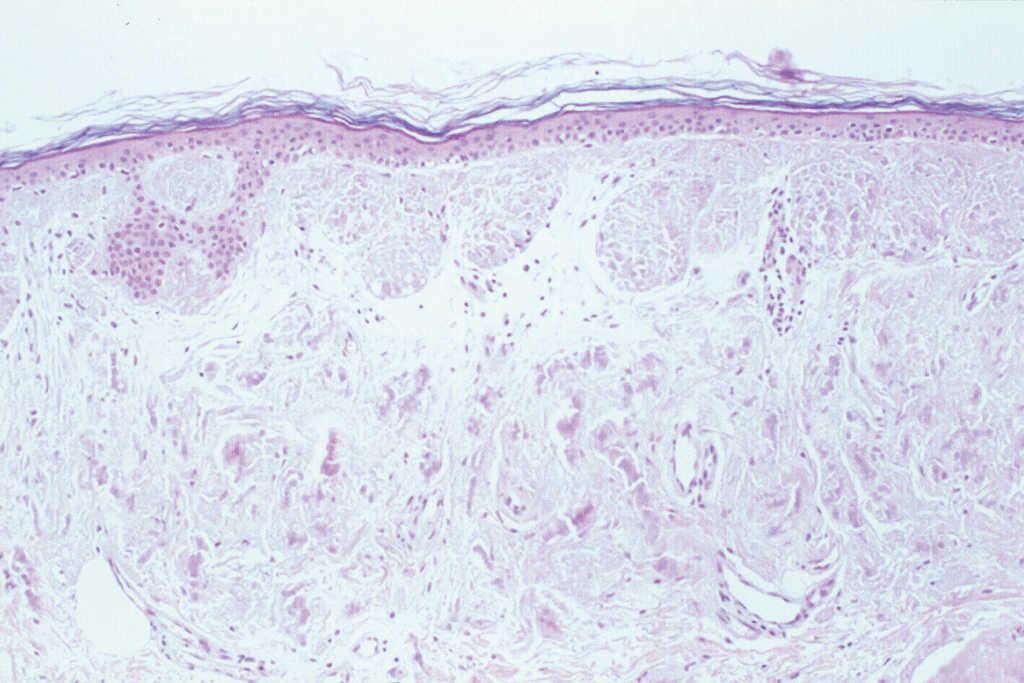

El hemograma, la velocidad de sedimentación globular (VSG), proteína C reactiva (PCR), coagulación, complemento, serología de virus de la hepatitis B y C (VHB y VHC), vitamina B12, ácido fólico, hormonas tiroideas, biomarcadores tumorales, inmunoglobulinas y orina (sedimento e inmunoelectroforesis) no mostraron alteraciones significativas. Las proteínas totales estaban aumentadas: 8,8 g/dl (VN: 6,6-8-3). El estudio electroforético de las proteínas evidenció un aumento de la gammaglobulina: 31,6 % (VN: 12-19 %). No obstante, los estudios de paraproteinemia, tanto en suero como en orina, fueron negativos. El factor reumatoide estaba elevado a 414 U/ml (0-20), y el estudio de autoinmunidad mostró ANA a títulos de 1/640, con patrón granular, anti-SSA/Ro superior a 100 U/ml (VN: 0-25), anti-SSB/La de 99,63 U/ml (VN: 0-25), con el resto de autoanticuerpos dentro de los límites de la normalidad. El estudio histopatológico de la lesión puso de manifiesto una acumulación de material eosinófilo, amorfo y acelular, en los dos tercios superiores de la dermis. Este material se encontraba también depositado en la dermis más profunda a nivel perivascular y perianexial, en donde también existía un discreto infiltrado de células plasmáticas (fig. 2). Las tinciones con rojo Congo y tioflavina fueron positivas (fig. 3), pero el material no se teñía con la proteína A del amiloide. Sin embargo, las tinciones con antisueros de cadenas ligeras κ y λ fueron positivas, demostrando la existencia de células plasmáticas policlonales.

Fig. 2.--Presencia de acumulaciones de un material eosinófilo, acelular y amorfo en la dermis, con presencia de células plasmáticas. (Hematoxilina-eosina, x20.)